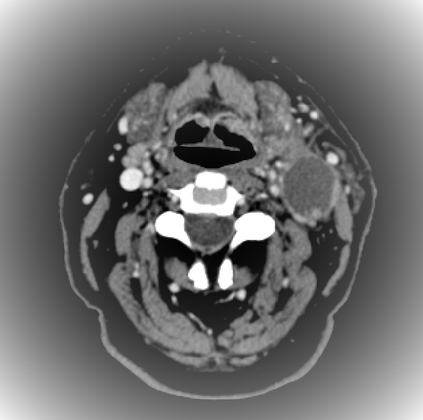

Organ at risk (OAR) segmentation is a critical process in radiotherapy treatment planning such as head and neck tumors. Nevertheless, in clinical practice, radiation oncologists predominantly perform OAR segmentations manually on CT scans. This manual process is highly time-consuming and expensive, limiting the number of patients who can receive timely radiotherapy. Additionally, CT scans offer lower soft-tissue contrast compared to MRI. Despite MRI providing superior soft-tissue visualization, its time-consuming nature makes it infeasible for real-time treatment planning. To address these challenges, we propose a method called SegReg, which utilizes Elastic Symmetric Normalization for registering MRI to perform OAR segmentation. SegReg outperforms the CT-only baseline by 16.78% in mDSC and 18.77% in mIoU, showing that it effectively combines the geometric accuracy of CT with the superior soft-tissue contrast of MRI, making accurate automated OAR segmentation for clinical practice become possible. See project website https://steve-zeyu-zhang.github.io/SegReg